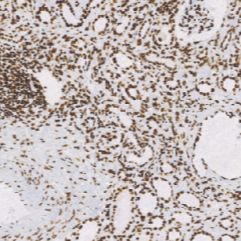

ARID1A是SWI/SNF染色质重塑复合物中的一个亚基,具有DNA结合活性。ARID1A蛋白在肿瘤中频繁缺失,ARID1A基因的突变足以实现肿瘤的发生。此抗体在脾脏,胸腺、前列腺、睾丸、卵巢、小肠和结肠中高度表达,据报道,在卵巢透明细胞癌中,ARID1A蛋白低表达导致低生存率,在宫颈腺癌中,约有9%的阳性率;在子宫内膜癌中有约30%的阳性率。

- 阳性部位:胞核

- 适用组织:石蜡切片

- 预处理:热修复